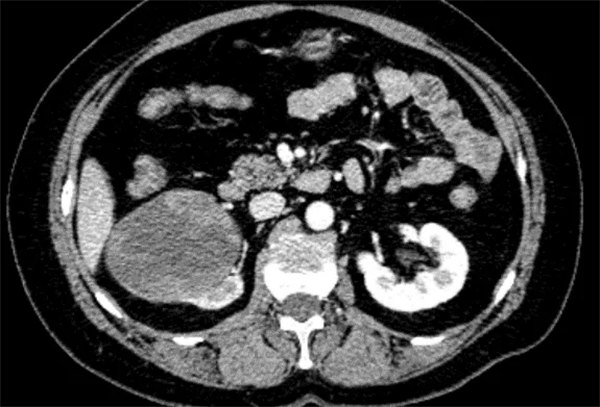

51歲的杜女士近半年來反復出現肉眼血尿, 多次至社區醫院就診,予消炎治療后癥狀稍好轉,但癥狀反反復復,近1周來出現了下腹部墜脹不適。

為了進一步治療至我院泌尿外科就診,完善下腹部、盆腔增強掃描+雙腎動脈CTA,經泌尿外科、醫學影像科等多個科室討論后一致診斷為惡性腫瘤。

匯報泌尿病院院長李穎毅,考慮患者腫瘤體積較大、呈膨脹性生長、突向腎竇。若經后腹腔手術,空間有限,且易損傷到腫瘤組織,科室高度重視患者病情,組織圍手術期相關的麻醉手術科、心內科、重癥醫學科、影像科等多個學科的專家進行多學科綜合會診(MDT),確定采用機器人輔助腹腔鏡技術,為患者實施機器人輔助腹腔鏡右腎根治性切除術”。

術中,手術團隊利用達芬奇機器人手術系統精準操作,充分游離暴露下腔靜脈、右腎動脈等重要血管結構,先夾閉并切斷右腎動脈,再依次阻斷下腔靜脈遠端、左腎靜脈、下腔靜脈近端。阻斷后切開下腔靜脈,順利取出所有癌栓,縫合下腔靜脈切口,依次解除血管阻斷,期間患者血流動力學穩定。經過2小時的“戰斗”,患者右腎及腫瘤組織被完整切除,術中腫瘤組織未受到損傷,出血量少,術后第二天患者即進食并下床活動。